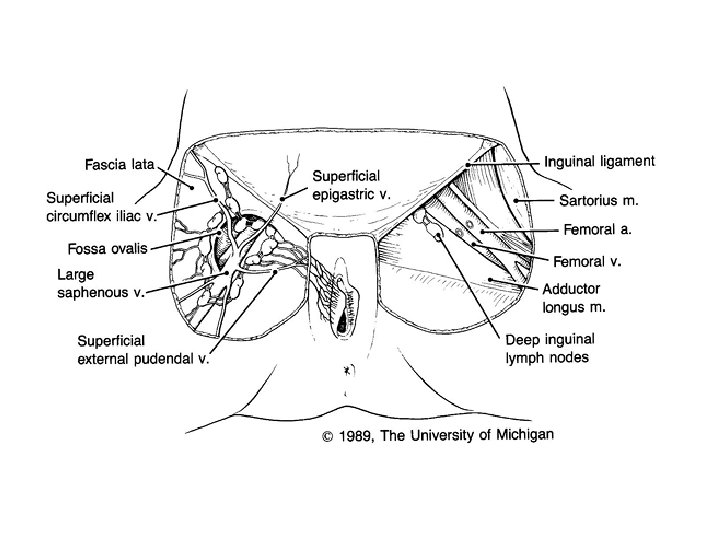

Lymph Drainage • The external genitalia, anus, and anal canal drain to the superficial inguinal nodes • The lower one third of the vagina drains to the sacral nodes and the internal and common iliac nodes • The cervix drains to the external or internal iliac and sacral nodes